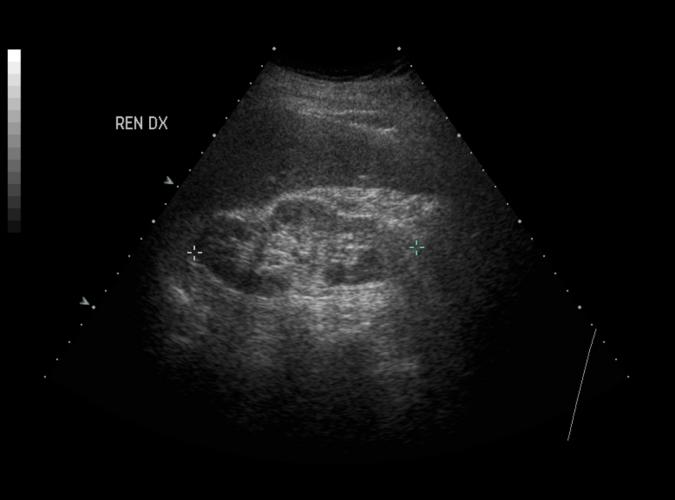

Post cholecystektomi patient. Normalvid gallgång i leverhilus (8a)...ändå choledochuskonkrement. Konkrement mellan kryssen. ERCP bekräftar.